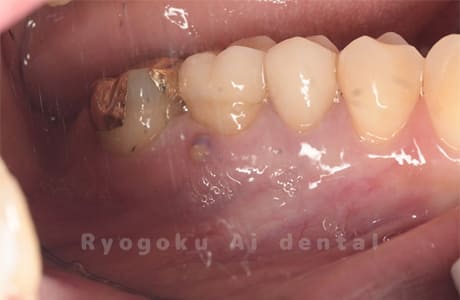

他院で治療した歯が腫れていて、様子を見るように言われたが、なかなか治らない、とのことでご来院された患者さんです。歯根端切除術を行い、腫れもなくなり、経過良好です。

<リスク・副作用>

外科手術のため、術後に出血、痛みや腫れ、違和感を伴います。口腔内の状態によっては適応できないことがあります。歯根端切除で治らなければ抜歯を検討しなくていけない場合もあります。